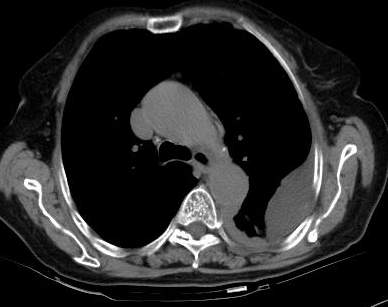

测ct值3-6hu,

既然ct值是3-6hu,还不如考虑包裹性积液。

请上传纵隔窗。目前还是支技包裹性积液(明显梭形),即使是间皮瘤并积液也少梭形的。

从图片看,包裹性积液好象更合理,梭形,ct值3-5hu(在哪看到的?);胸膜间皮瘤如此规则,不多见。

左侧背部胸膜肥厚,伴包裹性积液,不考虑间皮瘤.

同意以上各位的高见,首先考虑包裹性积液,1.胸膜间皮瘤积液量一般较大,以游离性积液更为常见,2.可以看到增厚的胸膜结节